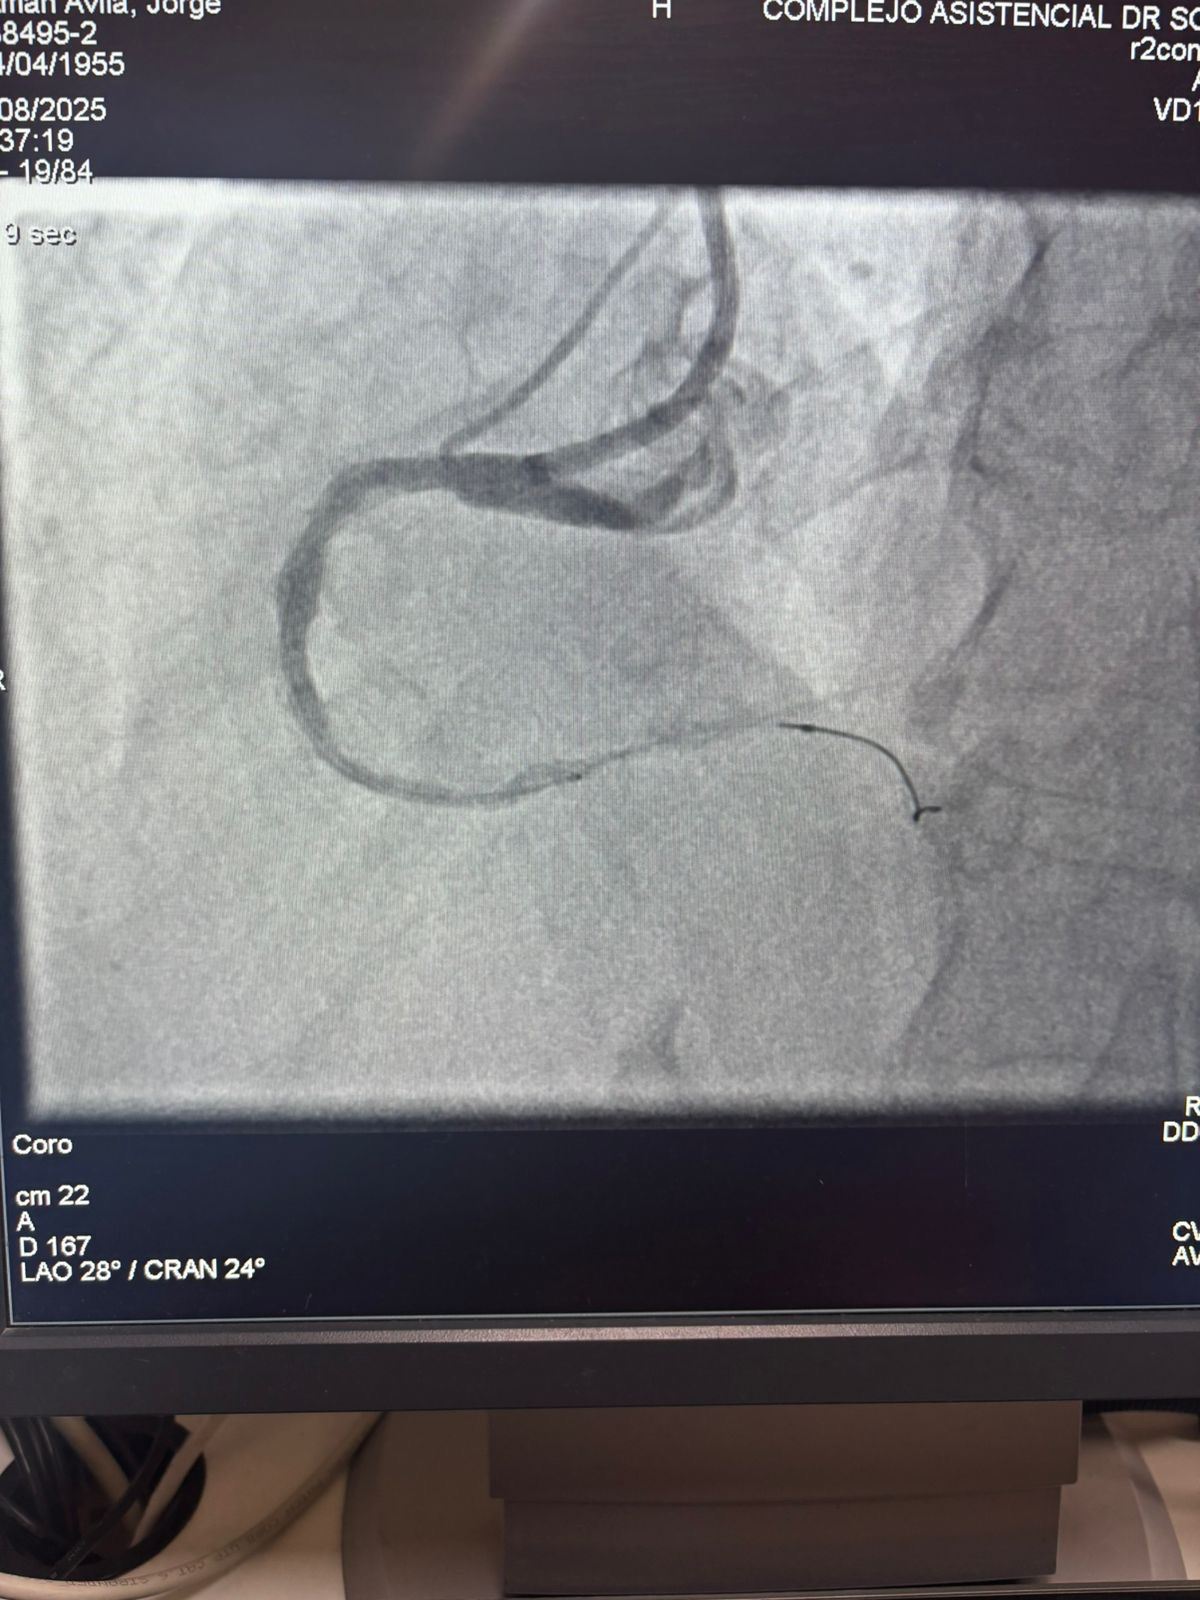

We are proud to share a remarkable case from Hospital Sótero del Río, Chile, where Dr. Martín Valdebenito successfully treated a heavily calcified lesion in the right coronary artery (first curve) using our Vesscrack Coronary IVL Balloon Dilatation Catheter System.

The procedure achieved outstanding results, with the calcified region effectively cracked and vessel flow restored. This marks another milestone in expanding global access to advanced solutions for complex coronary calcification.

The comparison between the pre-procedure and post-procedure angiographic images clearly demonstrates the significant clinical impact of our IVL technology.